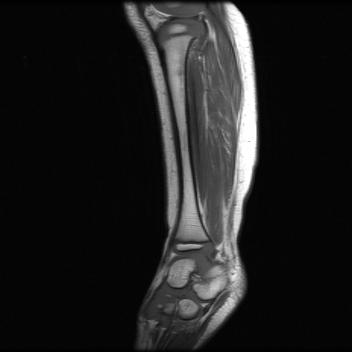

Test data: For evaluation, we used the ten 352352 MRI images in Fig. 2, which were not in the training dataset. The measurements were constructed using (1) with complex AWGN whose variance was adjusted to give a pre-masking SNR of 40 dB. For the multicoil experiments, we used coil sensitivities simulated using the Biot-Savart law, while in the single-coil case, we used .